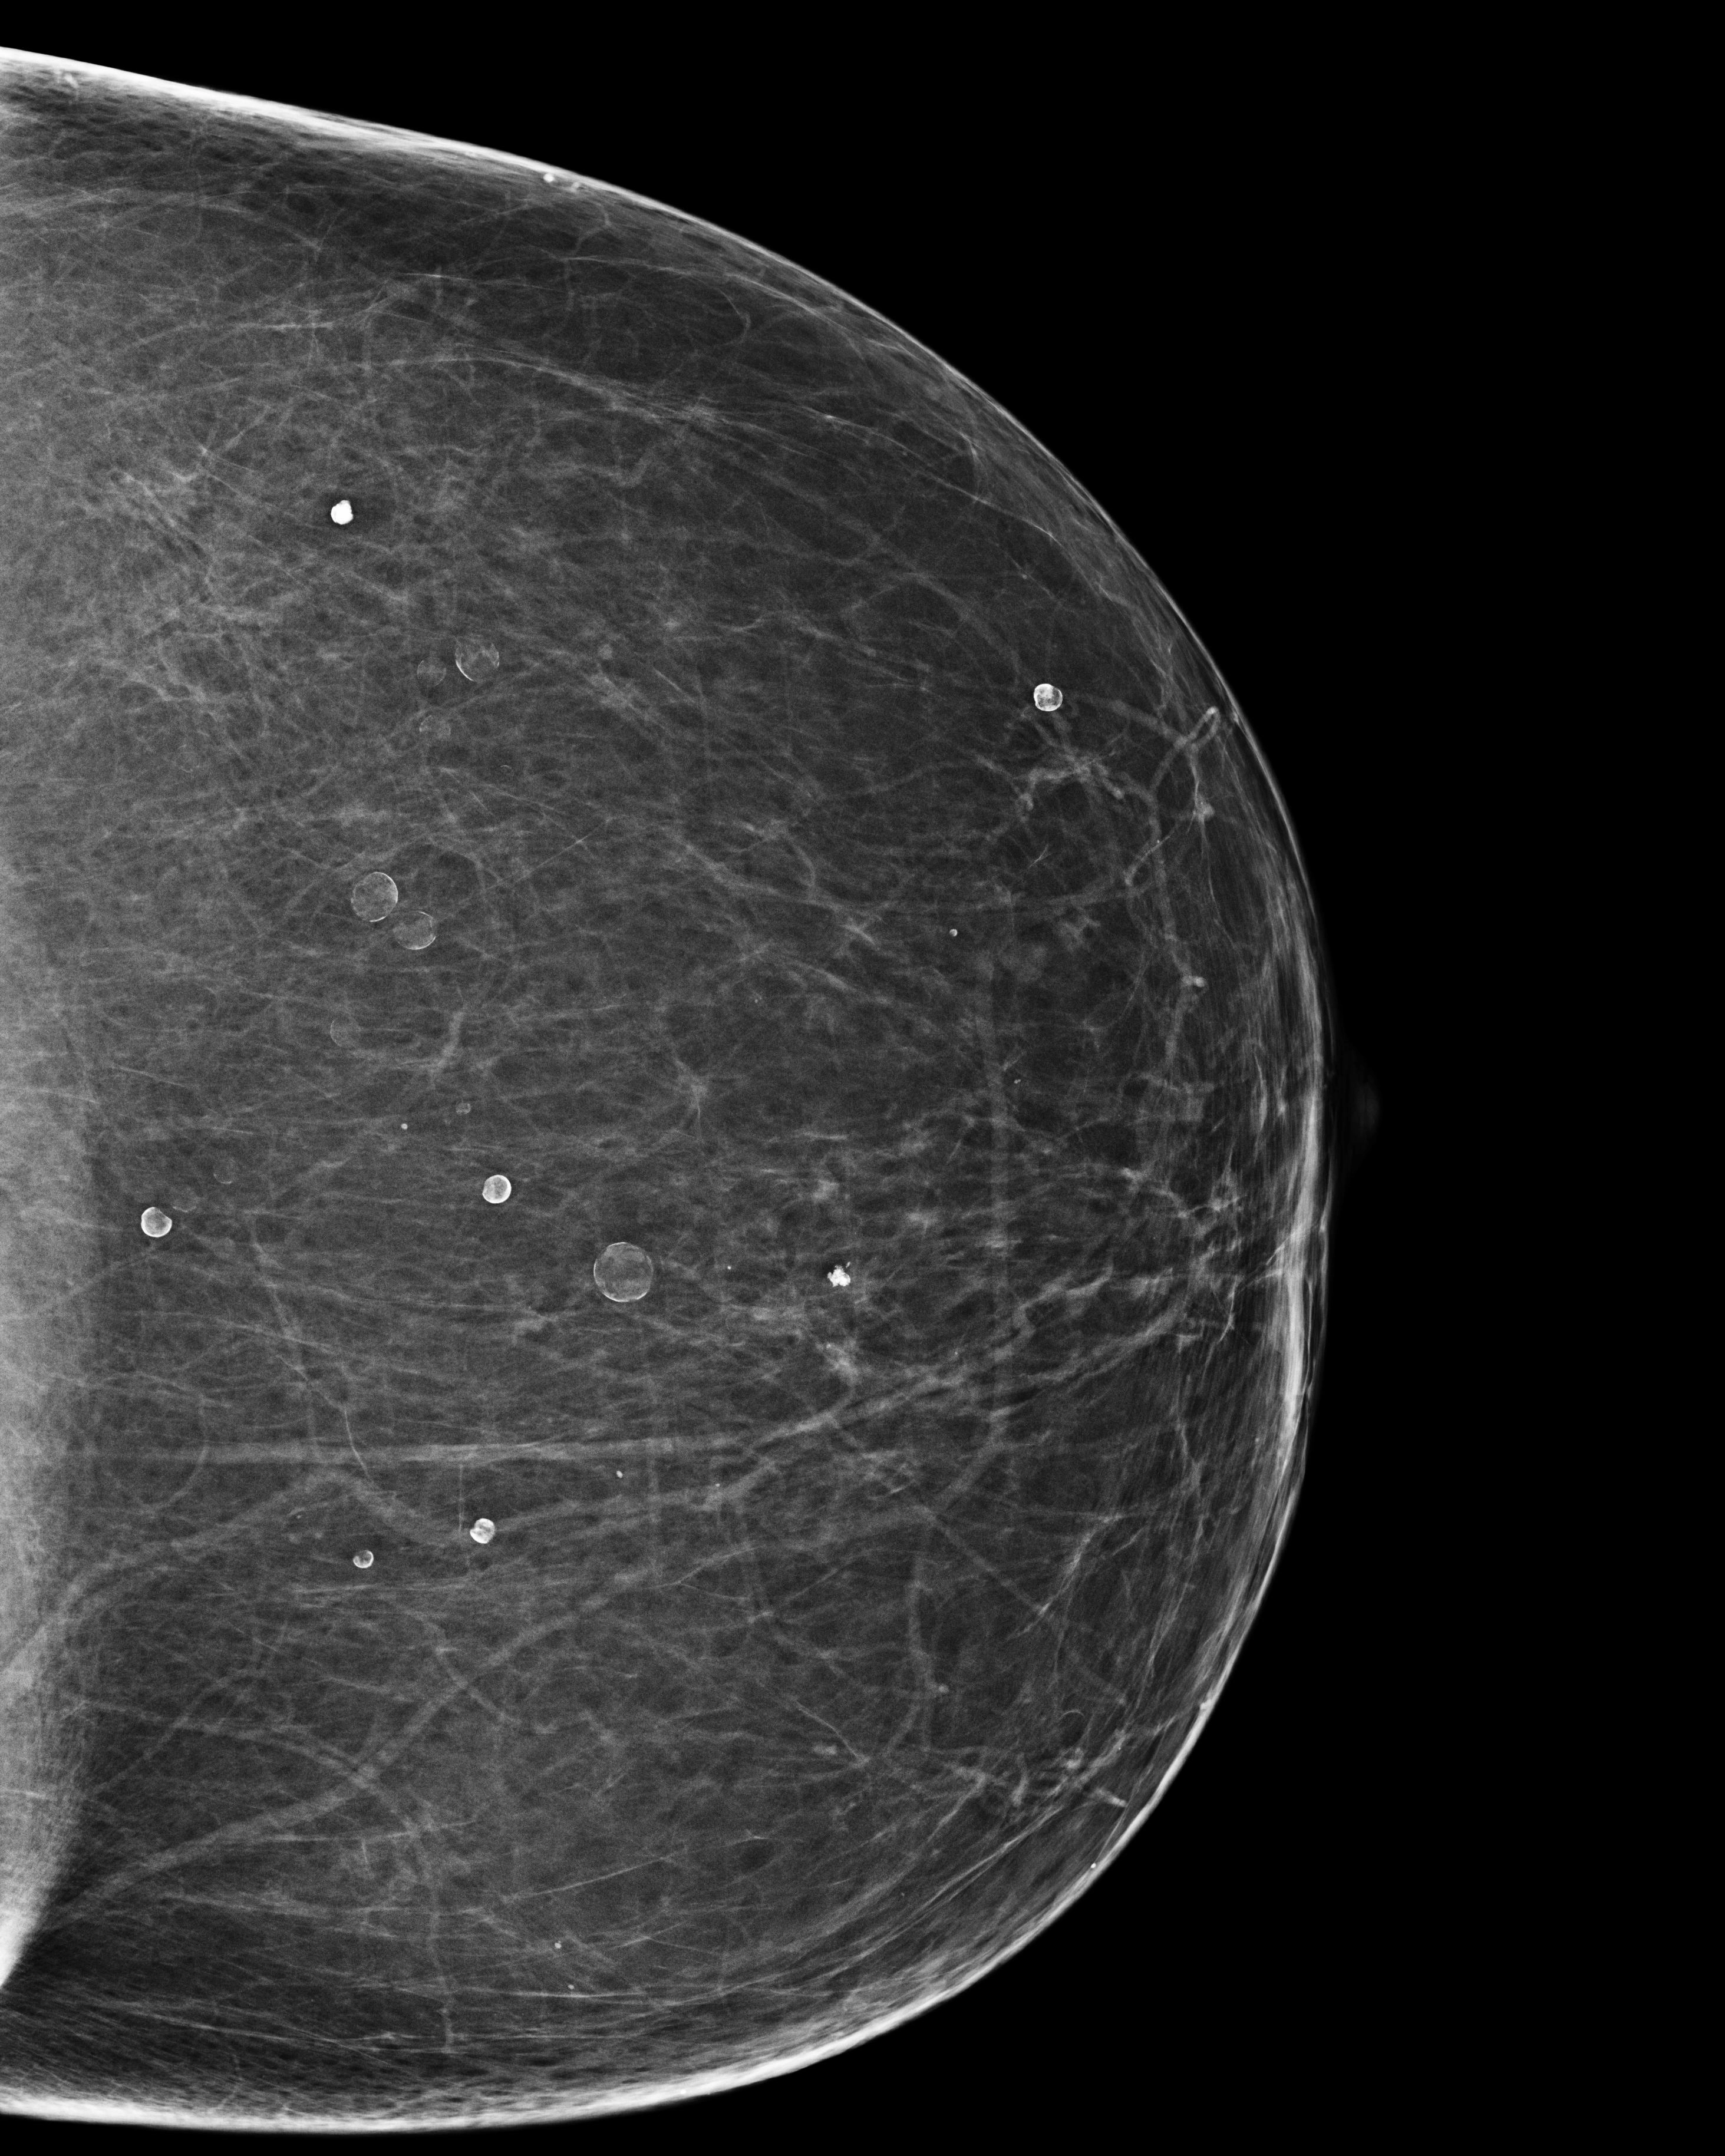

Vôi hóa tuyến vú (Breast calcifications)

Vôi hóa lành tính

Vôi hóa dạng tròn (Round breast calcifications)

Vôi hóa dạng vỏ trứng (Eggshell calcification (breast))